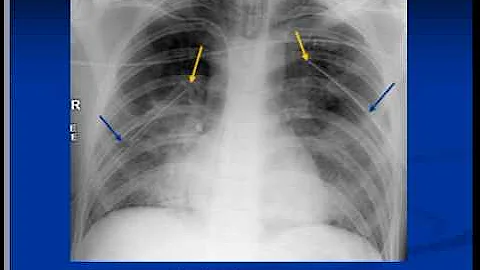

Introduction to several lines, tubes, and devices on chest radiographs.